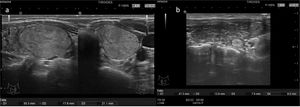

3 puntos: TIRADS 3 (probabilidad de malignizar 5%). Clasifica el nódulo como medianamente sospechoso. Se realizará seguimiento si el nódulo es ≥15mm y PAAF si el nódulo es ≥25mm en la ACR TI-RADS y en la EU TI-RADS>20mm (fig. 4 y video 3)

- –

4-6 puntos: TIRADS 4 (probabilidad de malignizar 20%). Clasifica el nódulo como moderadamente sospechoso. Se realizará seguimiento si el nódulo es ≥10mm y PAAF si el nódulo es ≥15mm (fig. 5 y video 4)